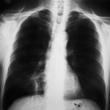

Pneumonia

Pneumonia is an infection in one or both of the lungs. Many germs, such as bacteria, viruses, and fungi, can cause pneumonia. You can also get pneumonia by inhaling a liquid or chemical. People most at risk are older than 65 or younger than 2 years of age, or already have health problems.

Your doctor will use your medical history, a physical exam, and lab tests to diagnose pneumonia. Treatment depends on what kind you have. If bacteria are the cause, antibiotics should help. If you have viral pneumonia, your doctor may prescribe an antiviral medicine to treat it.